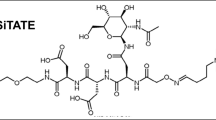

In the present study, we developed a possible tracer for meningiomas that is directed against the somatostatin receptor subtype 2 (SSTR2). We and others previously demonstrated overexpression of SSTR2 on all meningioma grades, making it a promising biomarker for binding [6,7,8,9,10,11]. Tyr3-octreotate, a previously generated peptide-analogue with a high affinity for SSTR2 [12], served as the meningioma specific binding part. Subsequent labelling with IRDye800CW yielded Ac-Lys0(IRDye800CW)Tyr3-octreotate (800CW-TATE). Here, we investigated the use of 800CW-TATE for suitability as a tracer in MFGS for meningiomas. Since both octreotate and IRDye800CW-tracers have been already applied in patients [13,14,15,16], this tracer is a promising candidate for clinical translation in meningioma surgery.

- 800CW-TATE:

-

Ac-Lys0 (IRDye800CW)Tyr3-octreotate

Supplementary file1 Chemical characteristics of 800CW-TATE. In order to form the investigated tracer 800CW-TATE, Tyr3-octreotate (depicted in black) was linked with Ac-lysine (depicted in blue) to the fluorescent dye IRDye800CW (depicted in green) (TIF 828 kb).